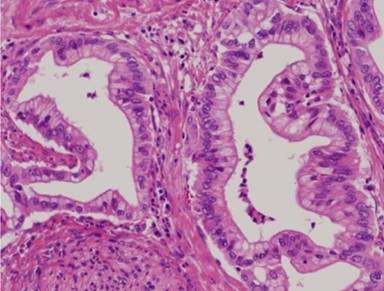

Histopathological examination of the resected lung mass showed that the tumor was composed of large, clear columnar epithelial cells arranged in atypical glandular structures. These morphological features were similar to those of the previously resected pancreatic cancer, and lung metastasis of pancreatic cancer was strongly suspected (Figures 4 and 5).

|

Figure 4. Primary pancreatic cancer specimen (x200). The tumor consists of atypical glandular structures. |